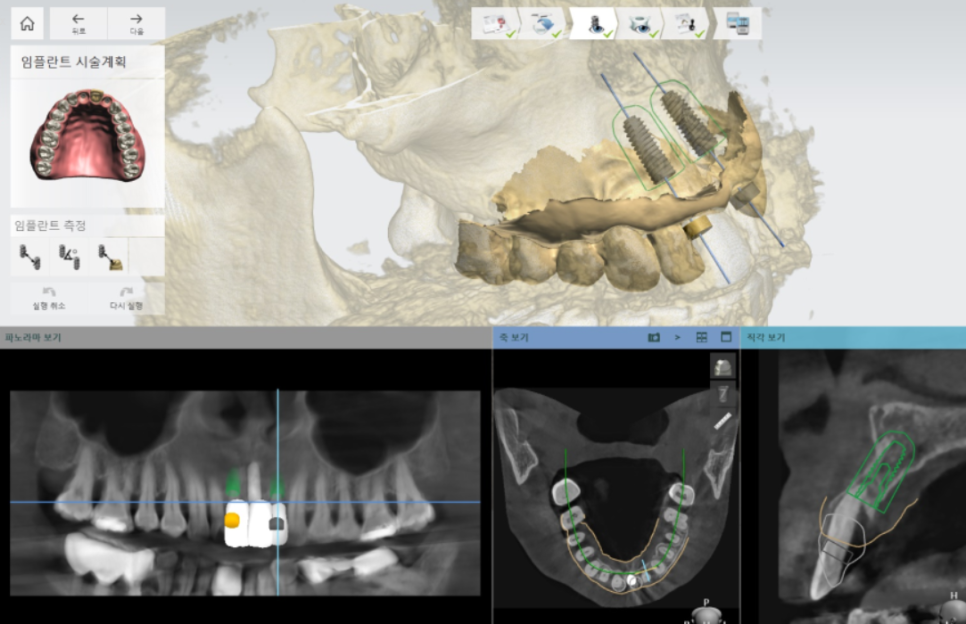

CT 진단 + 모의수술로 “각도와 위치” 확인

고덕동 임플란트, 튀어나온 앞니, 비용은 줄이고 자연스럽게 개선한 실제 사례

앞니 임플란트는

식립 위치와 각도가 결과를 좌우합니다.

조금만 달라도 보철이 앞으로 도드라져 보여

튀어나온 듯한 느낌이 들 수 있거든요.

그래서 저는 CT로 뼈 두께와

뼈 상태를 먼저 확인하고,

컴퓨터로 모의수술(가상 수술 계획)을 진행합니다.

231107

어느 위치에, 어느 각도로 들어가야

심미적으로 자연스럽고

기능적으로도 무리 없이 버티는지

수술 전에 미리 설계해두는 과정입니다.

이런 준비 덕분에 실제 수술에서도

계획했던 위치와 각도에 가깝게

차분하게 진행할 수 있었습니다. ^^